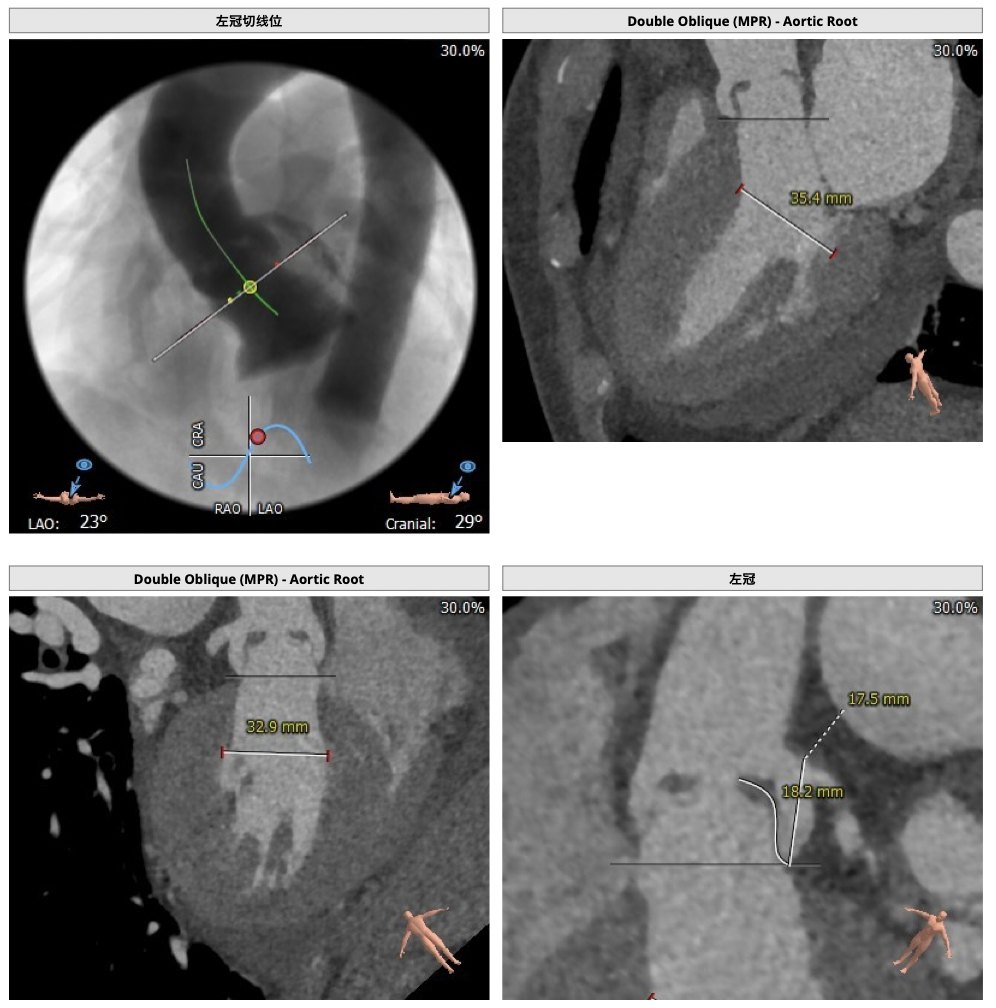

CT检查

②主动脉根部钙化较轻,瓣叶肥厚,各交界缘不同程度粘连,瓣膜释放后具有瓣周漏风险;

③左冠高度不高,且瓣叶冗长,达冠脉开口层面,且冠脉存在狭窄,存在冠脉阻塞的风险;

确保冠脉安全,拟采取PCI+TAVR一站式手术策略,因患者右侧股动脉钙化严重、入路狭窄,拟采取无鞘法从右股动脉穿刺入路,选用20mm球囊预扩、L23号VenusA-Valve瓣膜、采用VenusA-Plus输送系统确保瓣膜的精确释放,瓣膜释放后结合造影和超声情况,决定是否后扩。